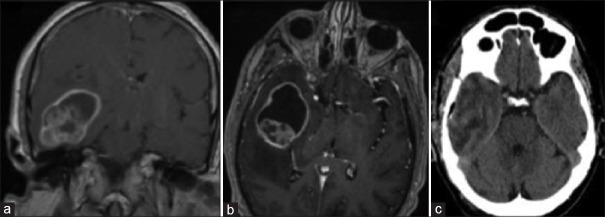

Pleomorphic xanthoastrocytoma with anaplastic features.

Brain Circ. 2025 Apr 8;11(3):236-239. doi: 10.4103/bc.bc_71_24. eCollection 2025 Jul-Sep.